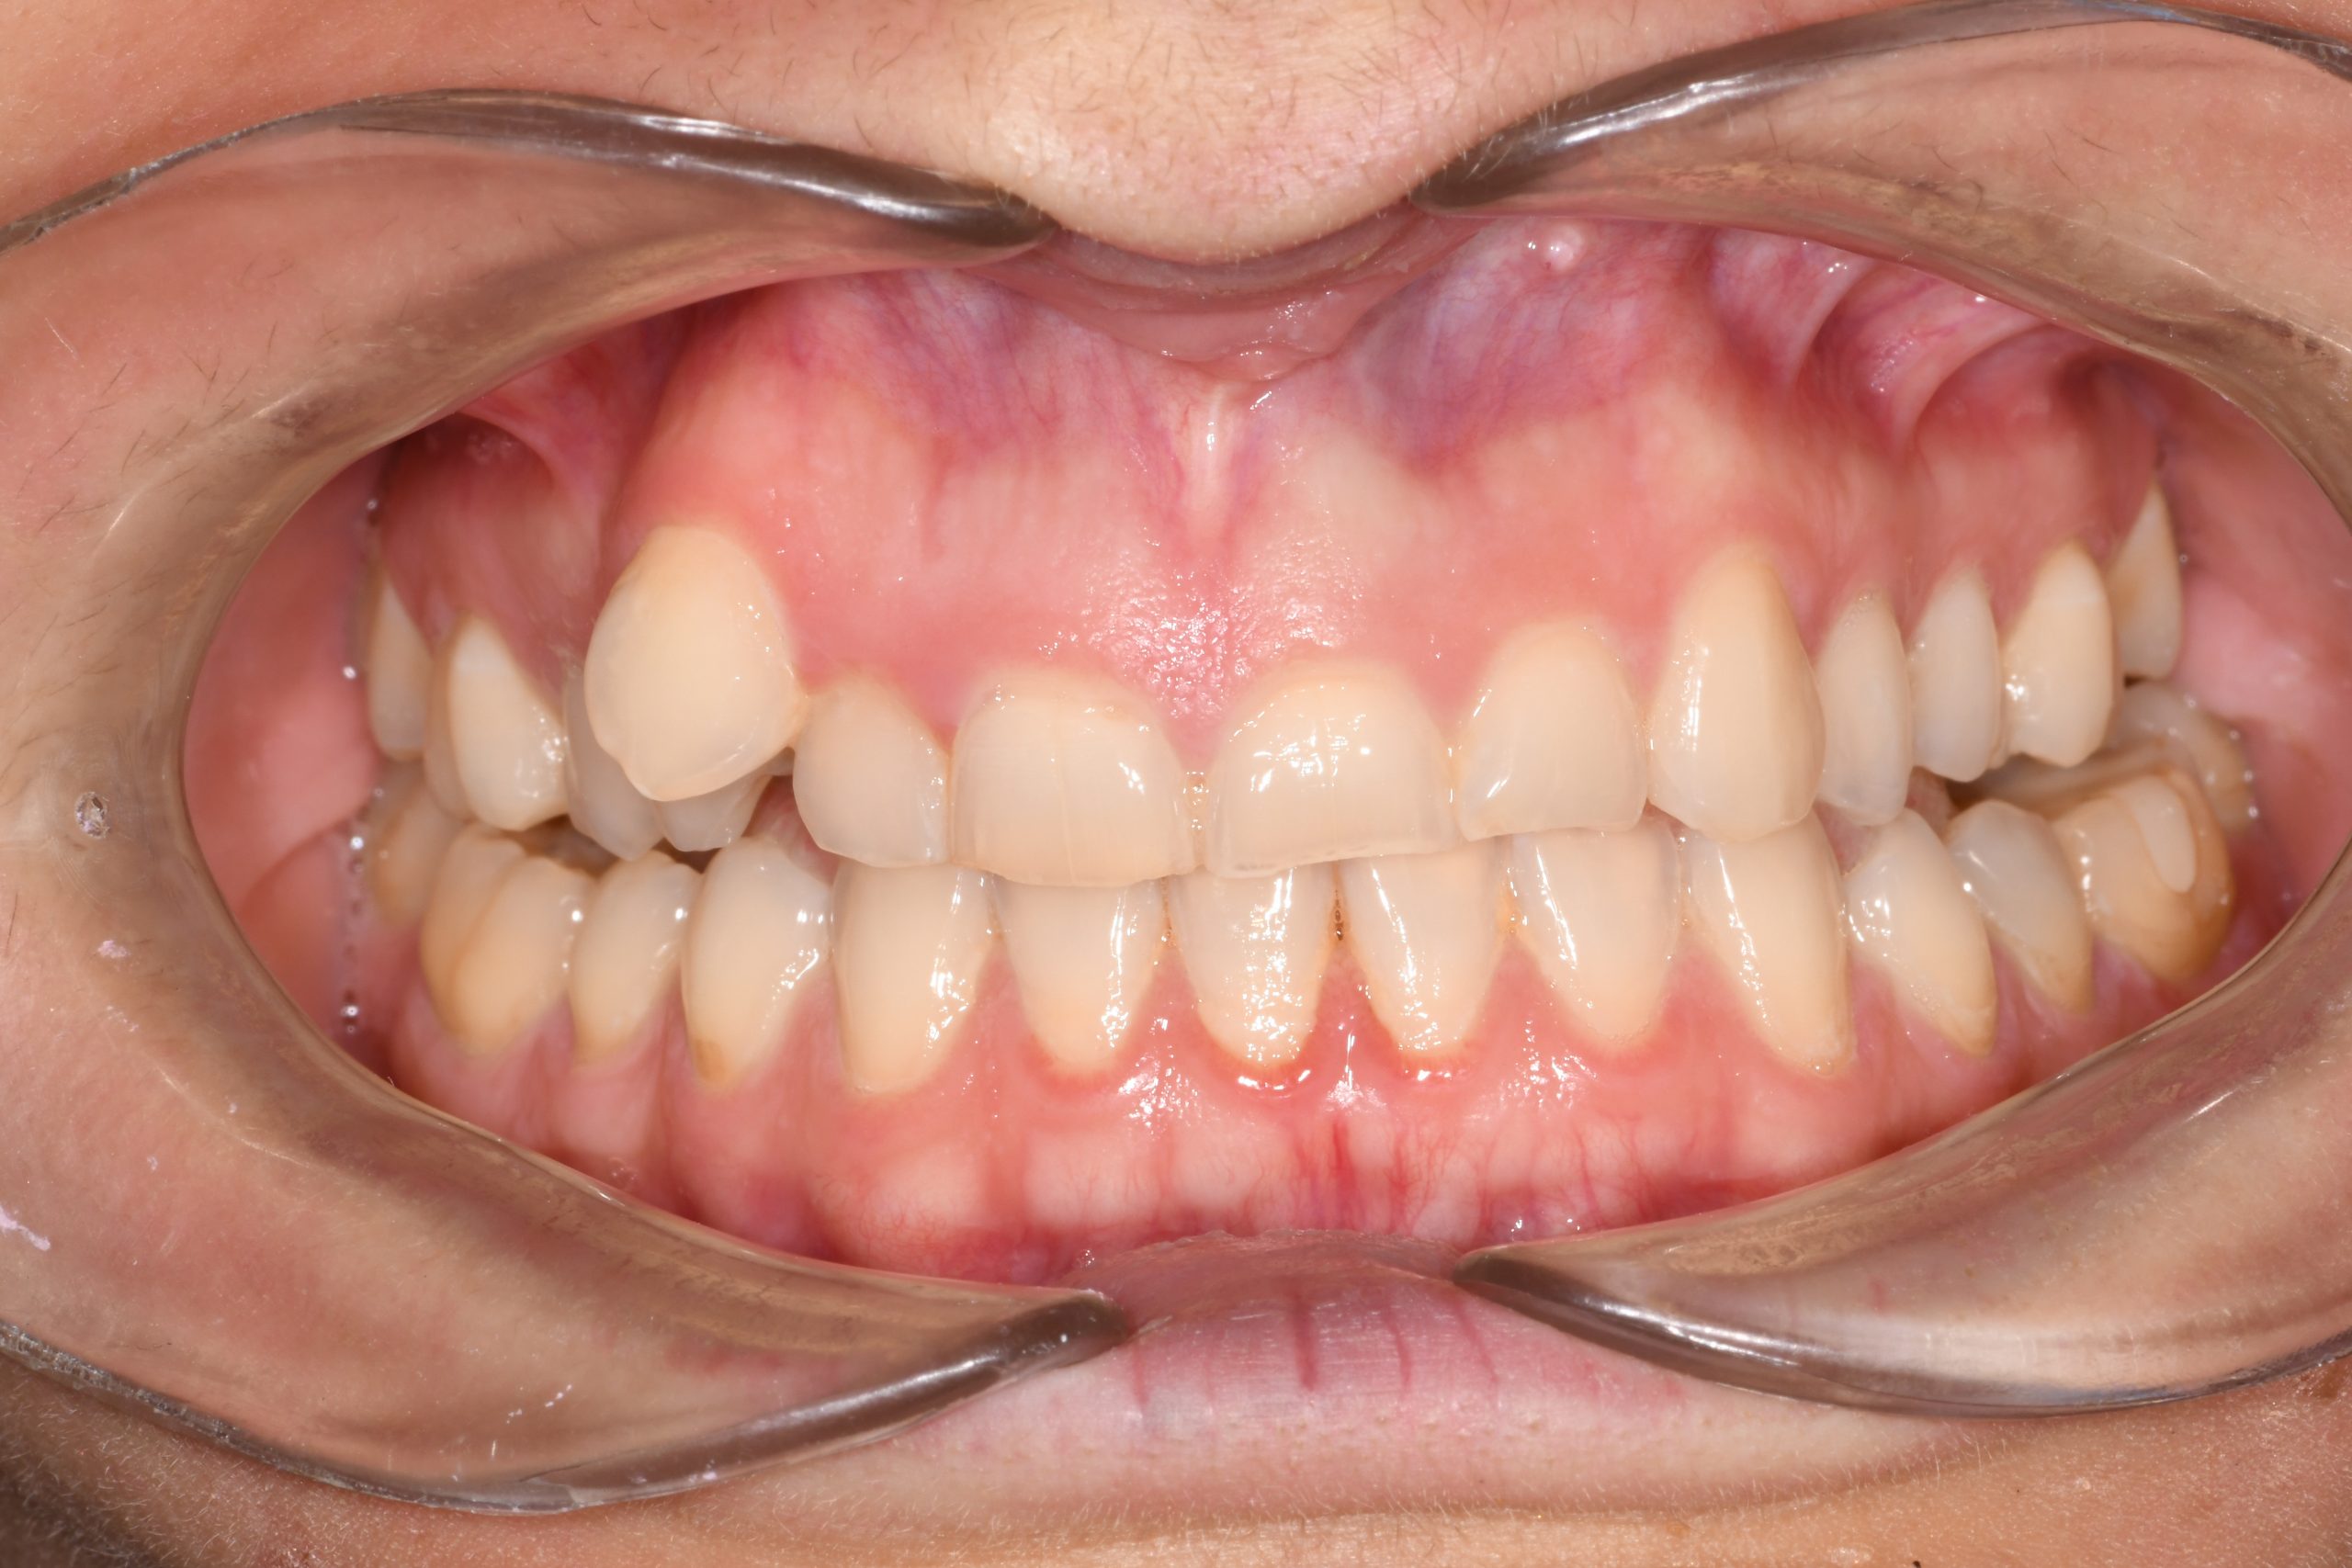

Az elmúlt évekből rengeteg szakmai referenciát tudnánk bemutatni, amelyek különböző fogszabályozási problémákat oldottak meg. Válogatva a több száz esetből, ezen az oldalon olyan képeket, információkat igyekeztünk bemutatni, amelyeknek a segítségével a jövőbeni pácienseinknek azt tudjuk üzenni: A Te fogsorod is lehet gyönyörű!

(Képeket a Pácienseink külön írásos beleegyezésével mutatjuk be!)